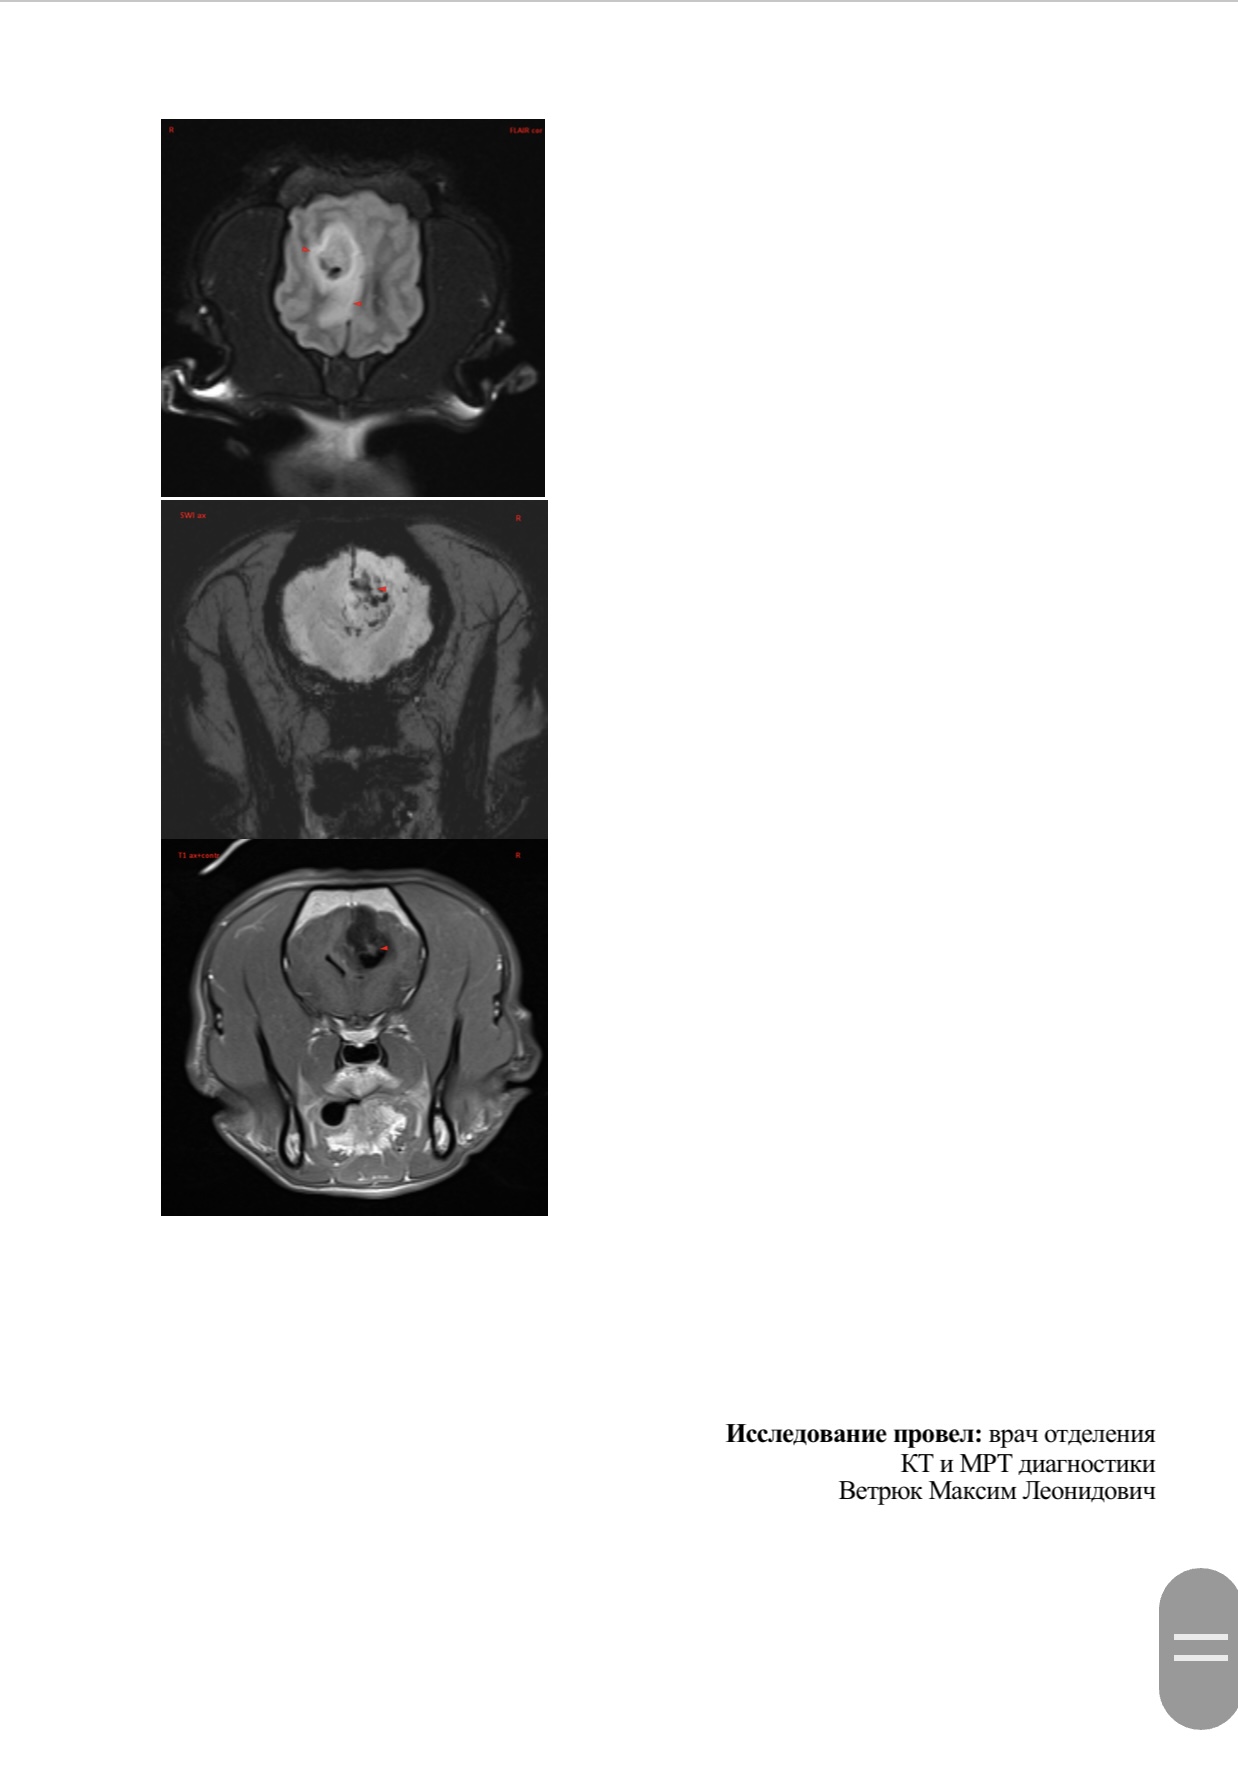

Вчера делали Марику МРТ в клинике Skolkovo Vet, если кому-то интересно, стоит чуть больше 12000₽. Результат неутешительный. Заключение:

МР-признаки новообразования в области лобной и теменной долей коры больших полушарий головного мозга справа, с очагами кровоизлияния и перифокальным отеком.

МР-признаки постсудорожных изменений.